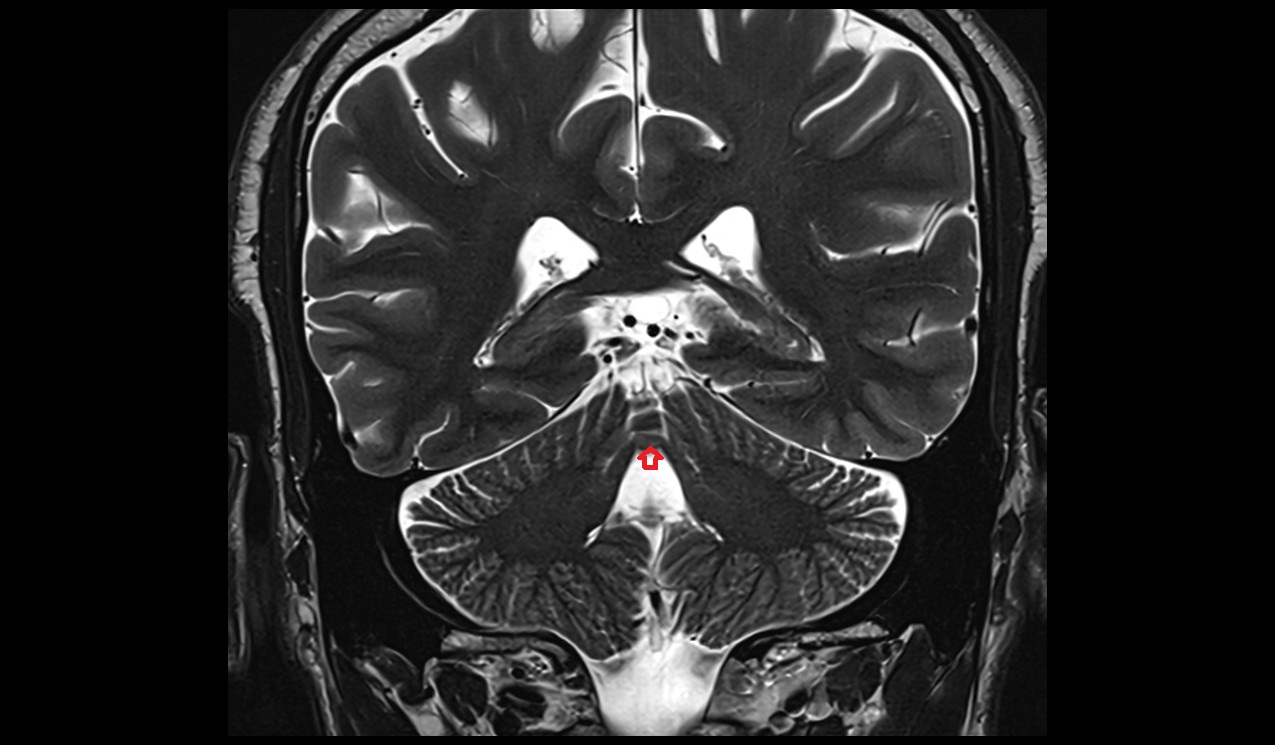

- Cerebellum

- Median aperture of fourth ventricle (foramen of Magendie)

- Cisterna magna